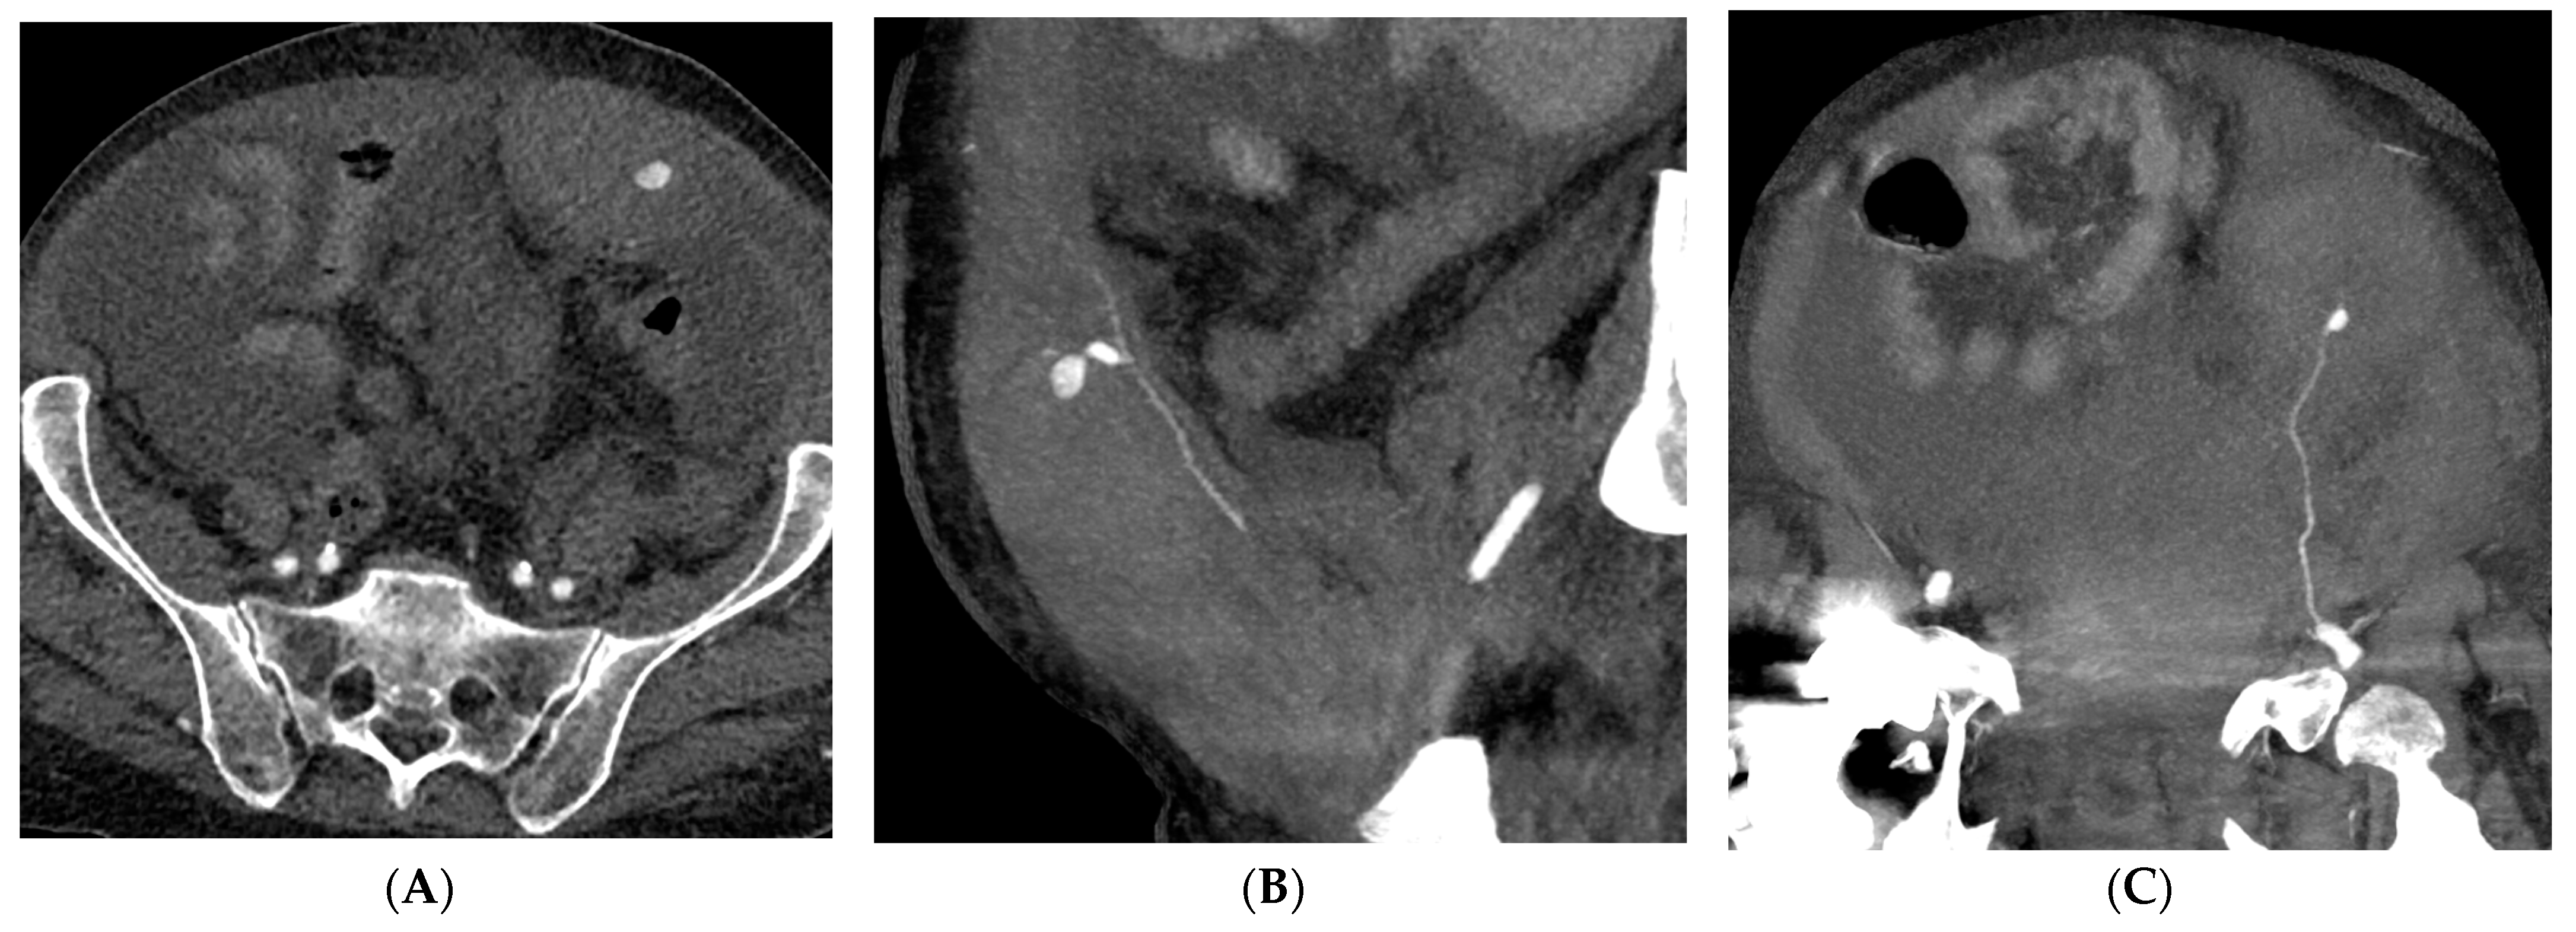

Figure 2. A 57-year-old man with coagulopathy, COVID-19, abdominal pain, and acute anaemia. (AC) CT angiography demonstrating a rectus sheath hematoma with a pseudoaneurysm of the left inferior epigastric artery depicted in the oblique sagittal and coronal planes by maximum intensity projection reformatting. (D) Digital Subtraction Angiography showing selective catheterization and pseudoaneurysm of the inferior epigastric artery. (E,F) Fluoroscopy showing the Onyx 34 cast distributed along the inferior epigastric artery and Digital Subtraction Angiography confirming successful embolization.